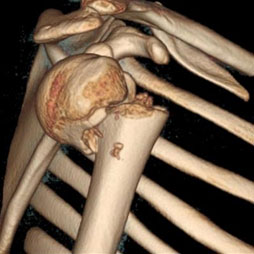

Validation of a Novel Radiographic View for Evaluating Proximal Humerus Fractures: The Clear View

Liane Chun, Amirhossein Misaghi, Krishna R. Cidambi, Natalie P. McNeil, Christine L. Farnsworth, Eric W. Edmonds